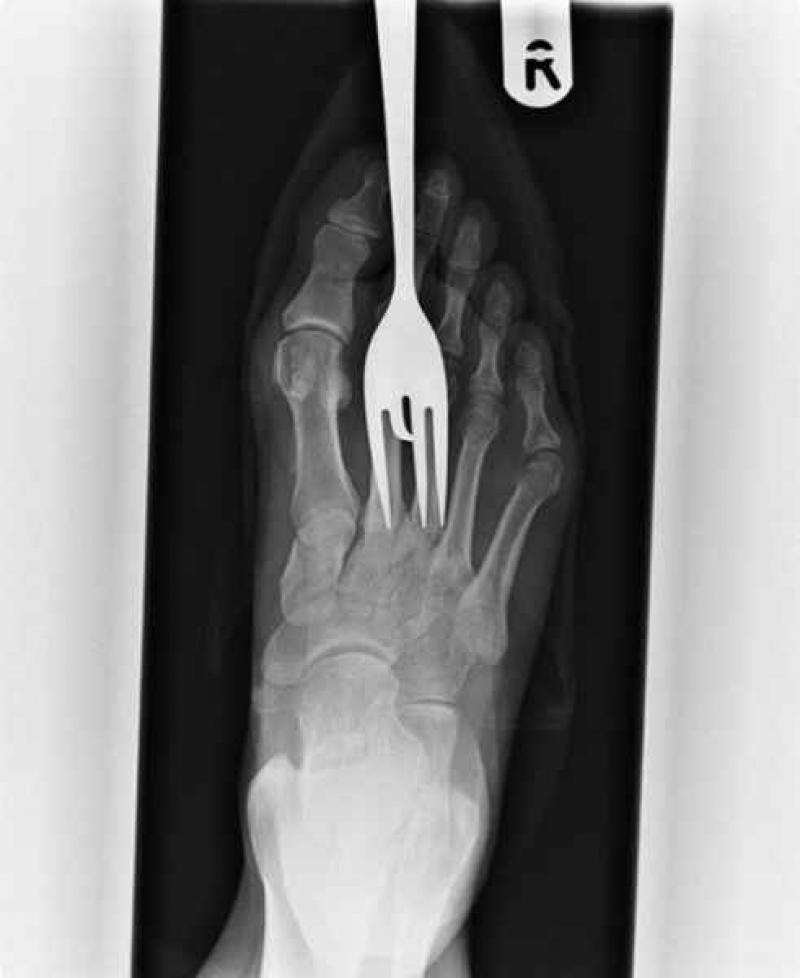

Röntgenfoto's zijn een medische uitvinding die ons al decennia lang helpt. Ze geven een nieuw gezichtspunt als het gaat om het vinden en behandelen van inwendige verwondingen. De machines kunnen opmerkelijke beelden vastleggen van het menselijk lichaam en ze documenteren vaak gruwelijke verwondingen. Een wonde van iemand zien, is al erg, maar als je ook kan zien wat de schade in het lichaam is, dat is nog veel erger. We hebben 12 tegelijk fascinerende, gruwelijke en hilarische röntgenfoto's op een rijtje gezet. Stel jezelf maar eens de vraag hoe iemand ooit aan die verwondingen is gekomen. We beginnen nog rustig.